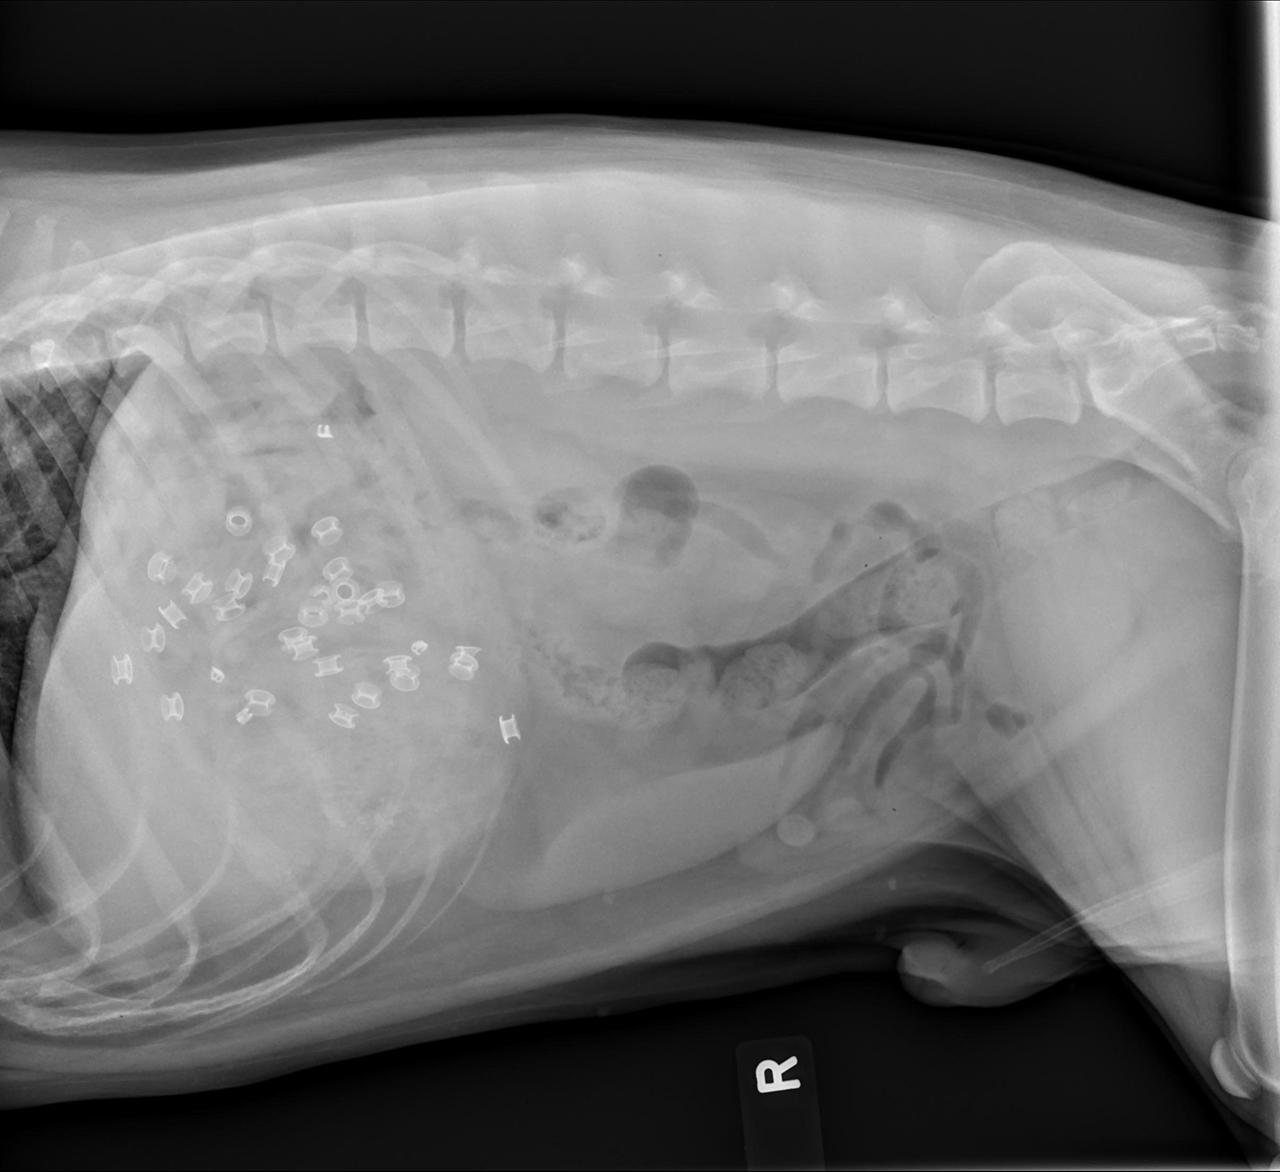

น้องหมาเขมือบท็อปบูต

ภาพเอกซเรย์พุงของเจ้า “วินซ์” สุนัขพันทาง อายุ 4 ปี ซึ่งเคี้ยวกินรองเท้าบูตหนังลูกวัวของนายมัน ที่บ้านในเมืองฟิลาเดลเฟีย ของสหรัฐอเมริกา เกือบหมดไปข้างหนึ่งจนพุงอืด ต้องรีบพาส่งศูนย์พยาบาลฉุกเฉินสัตวแพทย์โดยด่วน ผ่าท้องเอาออกมา หมอบอกว่ามันคงจะหายเป็นปกติดีในไม่ช้า.